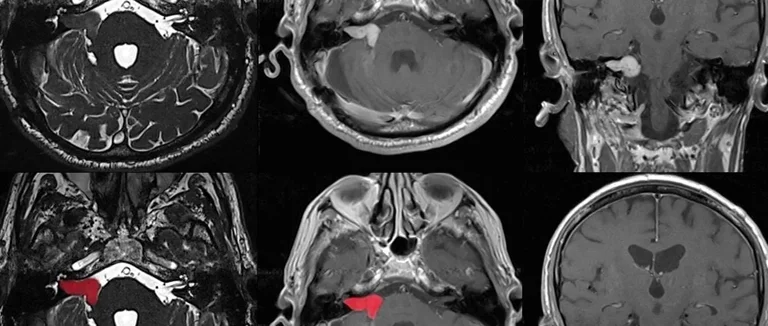

Диагностика и Лечение

Раннее выявление и лечение могут улучшить жизнь пациентов с доброкачественной опухолью мозга. Мы применяем современные методы для точной диагностики. Это помогает нам определить тип и местоположение опухоли.

Методы диагностики

Для диагностики используются МРТ (Магнитно-резонансная томография) и КТ (Компьютерная томография). Эти методы помогают нам точно узнать размер, форму и местоположение опухоли.

Могут проводиться дополнительные исследования, например, биопсия. Это помогает подтвердить диагноз и определить тип опухоли.